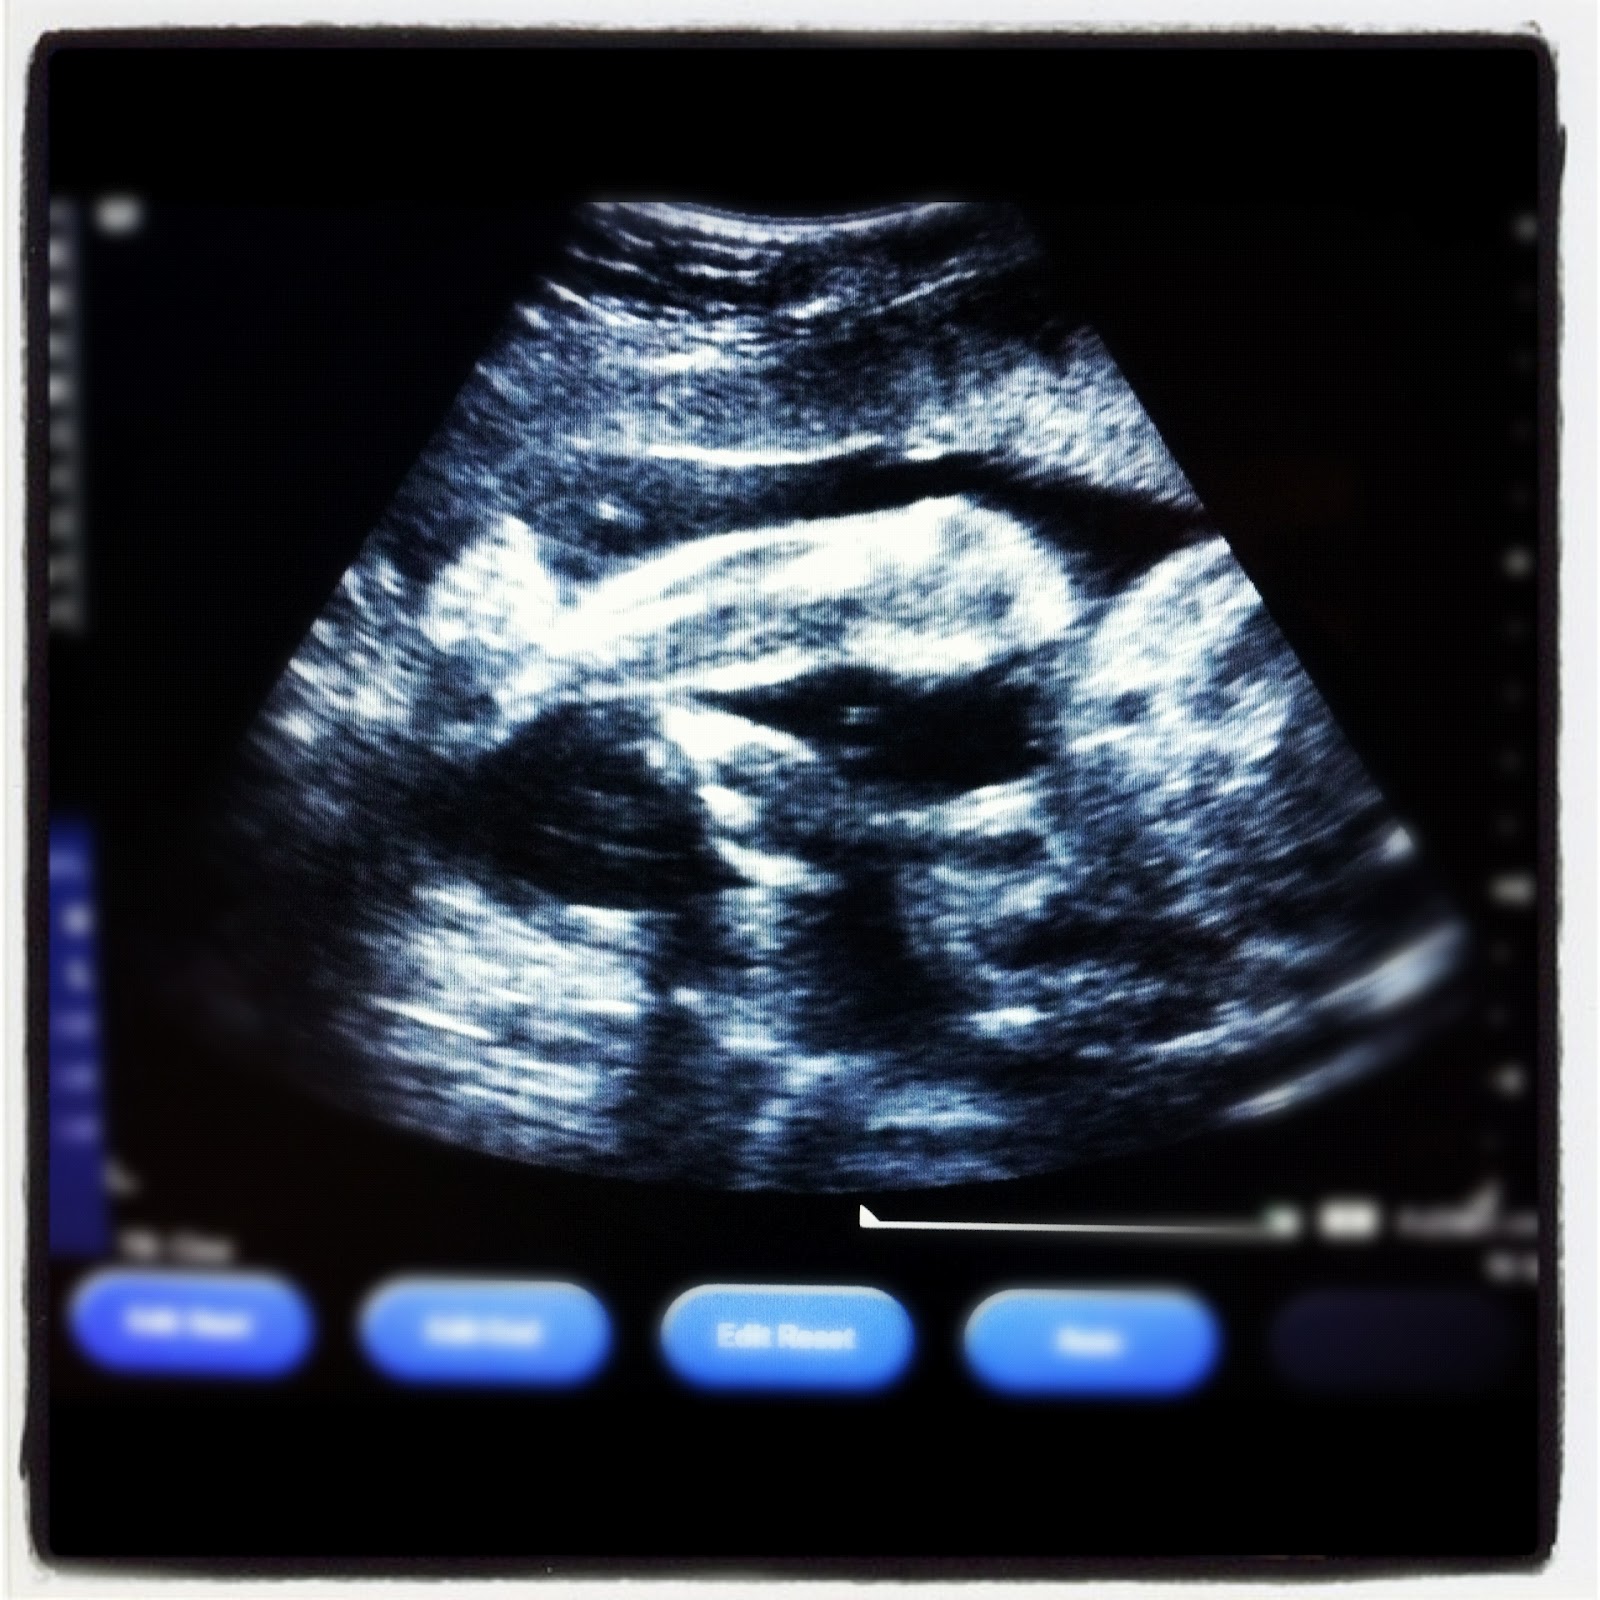

Today was the last day of my OB rotation; last for my intern year too (it's bittersweet since I love me some babies). This afternoon I was practicing OB ultrasounds, we got a glimpse of Cletus (the fetus) kicking back and fanning his/her toes... Nice beer belly there Clet...

-chillin-like-a-villain-